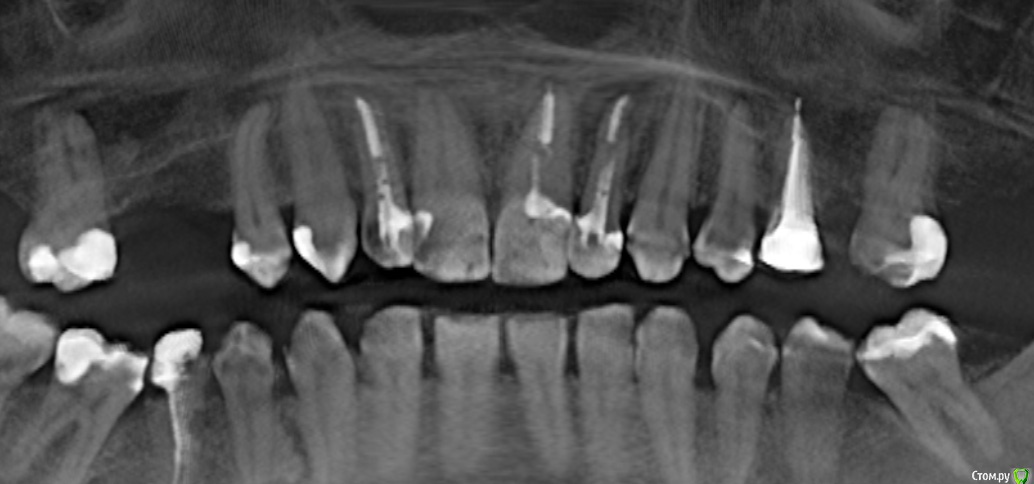

Ankazabolevshaya Опубликовано 28 мая, 2016 Поделиться Опубликовано 28 мая, 2016 Здравствуйте, уважаемые врачи! Очень сильно нуждаюсь в вашей помощи. В 2013 мне лечили два передних зуба (клык и передний). Пломбировали каналы, но коронки не ставили. Этой зимой я почувствовала боль в передних зубах в районе челюсти. Раздражение в дёснах. Резь. Потом вылез какой-то пупырь на десне. Я думала, что это стоматит. Не верила тем, кто мне говорил про нужность обзорного снимка. Признаю свою глупость. Теперь, после КТ оказалось что у меня сломаны эти каналы, а под левым клыком пустота. А пупырь, как мне сказали - это выход свища.Мне предложили зуб удалять. Как-то восстанавливать эту пустоту. Потом делать имплантацию. Есть ли сегодня технологии, позволяющие восстанавливать это пространство под зубом без его удаления, с последующей коронкой на него? И ещё один вопрос: могло ли все это случится из-за какой-нибудь заразы, занесенной во время лечения этих двух зубов в 2013г. ? Так же был момент ранения слизистой левой ноздри, как раз над свищем, который на десне. Просто очень часто слизистая иссыхала в одном месте и я травмировала слизистую. Буду очень благодарна за ответ. От меня в клинике ждут решения, а я переживаю, что улыбка испортится с искусственным зубом. Зуб этот свой очень люблю. Анна. Ссылка на комментарий

red_butler Опубликовано 28 мая, 2016 Поделиться Опубликовано 28 мая, 2016 Спасибо! Можете пояснить, Вы думаете, что зуб можно спасти? если судить только по снимкам, то да 1 Ссылка на комментарий

Ankazabolevshaya Опубликовано 28 мая, 2016 Автор Поделиться Опубликовано 28 мая, 2016 если судить только по снимкам, то даа скажите, как по Вашему, это киста прикорневая? Или челюсть разрушена? Нужно восстановление челюсти? Ссылка на комментарий

Ankazabolevshaya Опубликовано 28 мая, 2016 Автор Поделиться Опубликовано 28 мая, 2016 если судить только по снимкам, то даи корень ведь сломан, поставить под коронки всё равно можно? Ссылка на комментарий

red_butler Опубликовано 29 мая, 2016 Поделиться Опубликовано 29 мая, 2016 а скажите, как по Вашему, это киста прикорневая? Или челюсть разрушена? Нужно восстановление челюсти? это не важно и корень ведь сломан, поставить под коронки всё равно можно? перелома не увидел И еще последнее, как Вы относитесь к процедуре - депофорез? В моём случае стоит в эту торону смотреть? бесполезно 2 Ссылка на комментарий

red_butler Опубликовано 29 мая, 2016 Поделиться Опубликовано 29 мая, 2016 Как же доказать им что нет на самом деле этого перелома (или корневого канала)? Мы видим только часть срезов Кт, а доктора на очном осмотре и ситуацию в полости рта.Сходите еще на пару консультаций. Как по-вашему – скорее всего виноват тот врач (как раз это тот врач, который настаивает на удалении и на переломе канала), который пломбировал каналы этого зуба в 2013? Или я? Сколько по времени такая штука на корне в среднем формируется? Было и ранение слизистой носа было так же ранение десны во время читки нитью, глубокое и долго заживало. Теперь уже не разобраться, виноват ли врач? Вы не правильно понимаете цели форума, Мы отвечаем на вопросы "что делать" Да и раз депофорез бесполезен, то что с Вашей точки зрения предпочтительнее сегодня в моём случае? Лазер или иссечение корня? Повторное лечение корневого канала. 3 Ссылка на комментарий

Ankazabolevshaya Опубликовано 31 мая, 2016 Автор Поделиться Опубликовано 31 мая, 2016 Всем спасибо большое! Да, так и оказалось, что трещины нет. Отправляла снимки в пару Московских клиник и сходила к эндодантисту , который работает на микроскопе. Через канал всё промыли и заложили лекарство. В извлеченном материале из канала были какие-то чёрные включения. Т.е. пломбирование было не герметичным. Как мне сказали, 70% что заживёт. Если нет, тогда будут иссякать корень. И только если это не поможет, будет удаление. 1 Ссылка на комментарий

Ankazabolevshaya Опубликовано 29 июня, 2016 Автор Поделиться Опубликовано 29 июня, 2016 Здравствуйте! Сегодня вновь была у стоматолога. Ситуация такая (очень нехорошая): После того, как заложили лекарство - свищ так и не закрылся. Доктор очень удивился. Вновь заложил лекарство, но уже добавив какой-то йодсодержащий препарат. А затем сделал снимок (мне его не дал, поэтому собираюсь сделать кт снова). Рассматривая снимок, он очень сильно огорчился (даже оплату не взял за посещение). Сказал, что раньше через микроскоп ситуацию не увидел такой, какая она скорее всего является. Что это очень может быть - резорбция корня и скорее всего внутренняя. Что то, что мы сейчас сделали скорее всего не принесёт результата. И что если даже затянется свищ, хорошего всё равно мало...Отсечение корня не поможет – расстояния там какие-то маленькие, зуб упадёт от яблока...Доктор говорил про то, что можно чем-то залить, про штифт… не успевала фиксировать эти предположения и не смогла запомнить формулировки. Может быть всё зря? Или всё же стоит идти дальше? Доктор хороший, один из лучших в городе. Снимок после последних процедур постараюсь сделать и выложить побыстрее. Ссылка на комментарий